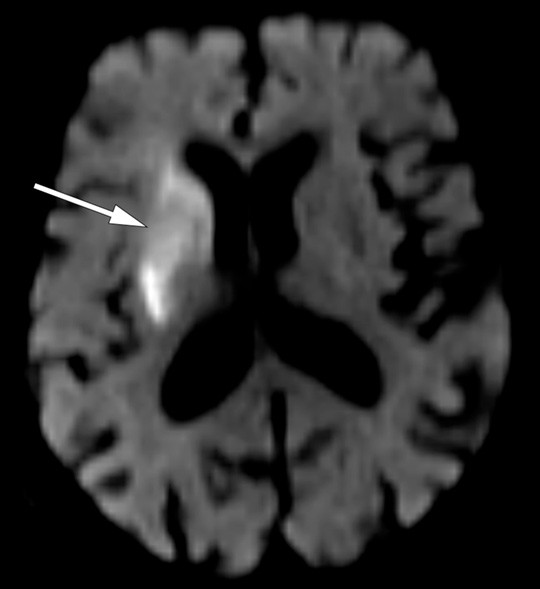

Pasienten hadde våknet med symptomene klokken 0625, og symptomdebut var ukjent. Det ble utført MR-caput etter oppvåkningsslag-protokoll («wake-up stroke») (DWI- og FLAIR-sekvens). Diffusjonsvektede bilder viste diffusjonsrestriksjon i høyre basalganglieregion og corona radiata (fig 1) med korrelerende lavsignal på ADC-kartet. FLAIR-sekvensen viste ingen sikre signalavvik i det affiserte området (fig 2). Dette tydet på at infarktforandringene var ferske, og klokken 0850 ble det derfor gitt intravenøs trombolytisk behandling. Etter at trombolytisk behandling var satt i gang ble det utført CT-angiografi av pre- og intracerebrale kar, som viste en okklusjon i proksimale del av arteria cerebri media (ACM) på høyre side. Pasienten ble raskt overflyttet til angiografilaben hvor det klokken 0940 ble igangsatt trombektomi, som var teknisk vellykket.